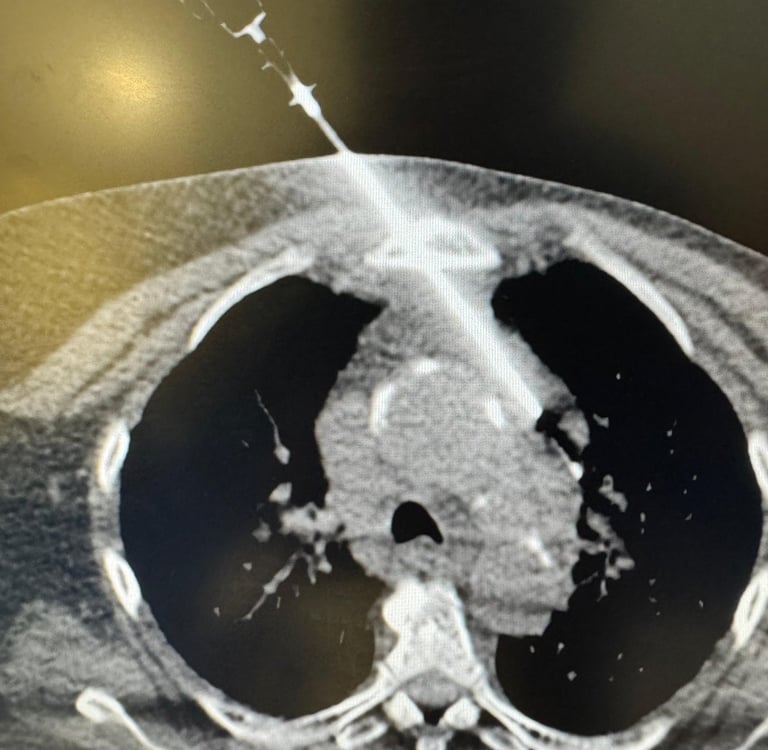

Ablações Percutâneas

Ablação por radiofrequência (RFA)

Ablação por micro-ondas

Crioablação

Ablação química (álcool, ácido acético)

Ablação de tumores hepáticos, renais, pulmonares, ósseos e de partes moles

Biópsias pulmonares